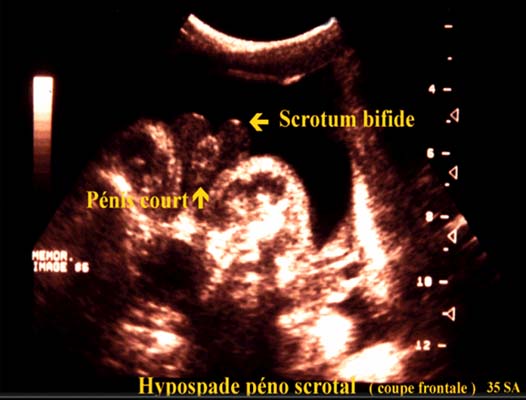

L’hypospade proximal ou péno scrotal est plus complexe et plus grave.

Dans sa forme majeure les bourrelets labio scrotaux ne fusionnent pas ce qui donne un aspect de bourse fendue, le pénis est de petite taille l’ensemble évoquant un sexe féminin.

L’existence des testicules dans les bourrelets est une aide au diagnostic.

Si les testicules restent dans les canaux inguinaux le tableau constitue un piège diagnostic et fait porter un diagnostic erroné de sexe féminin.